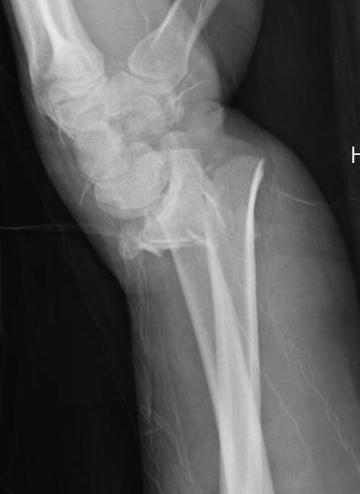

All fractures should be reduced initially and reassessed

- conscious sedation

- 2 minutes of traction / reduction of deformity

- backslab / elevation in gallows

- re-xray

Distal Radius Fracture Severely Displaced.jpgDistal Radius Post Reduction.jpg